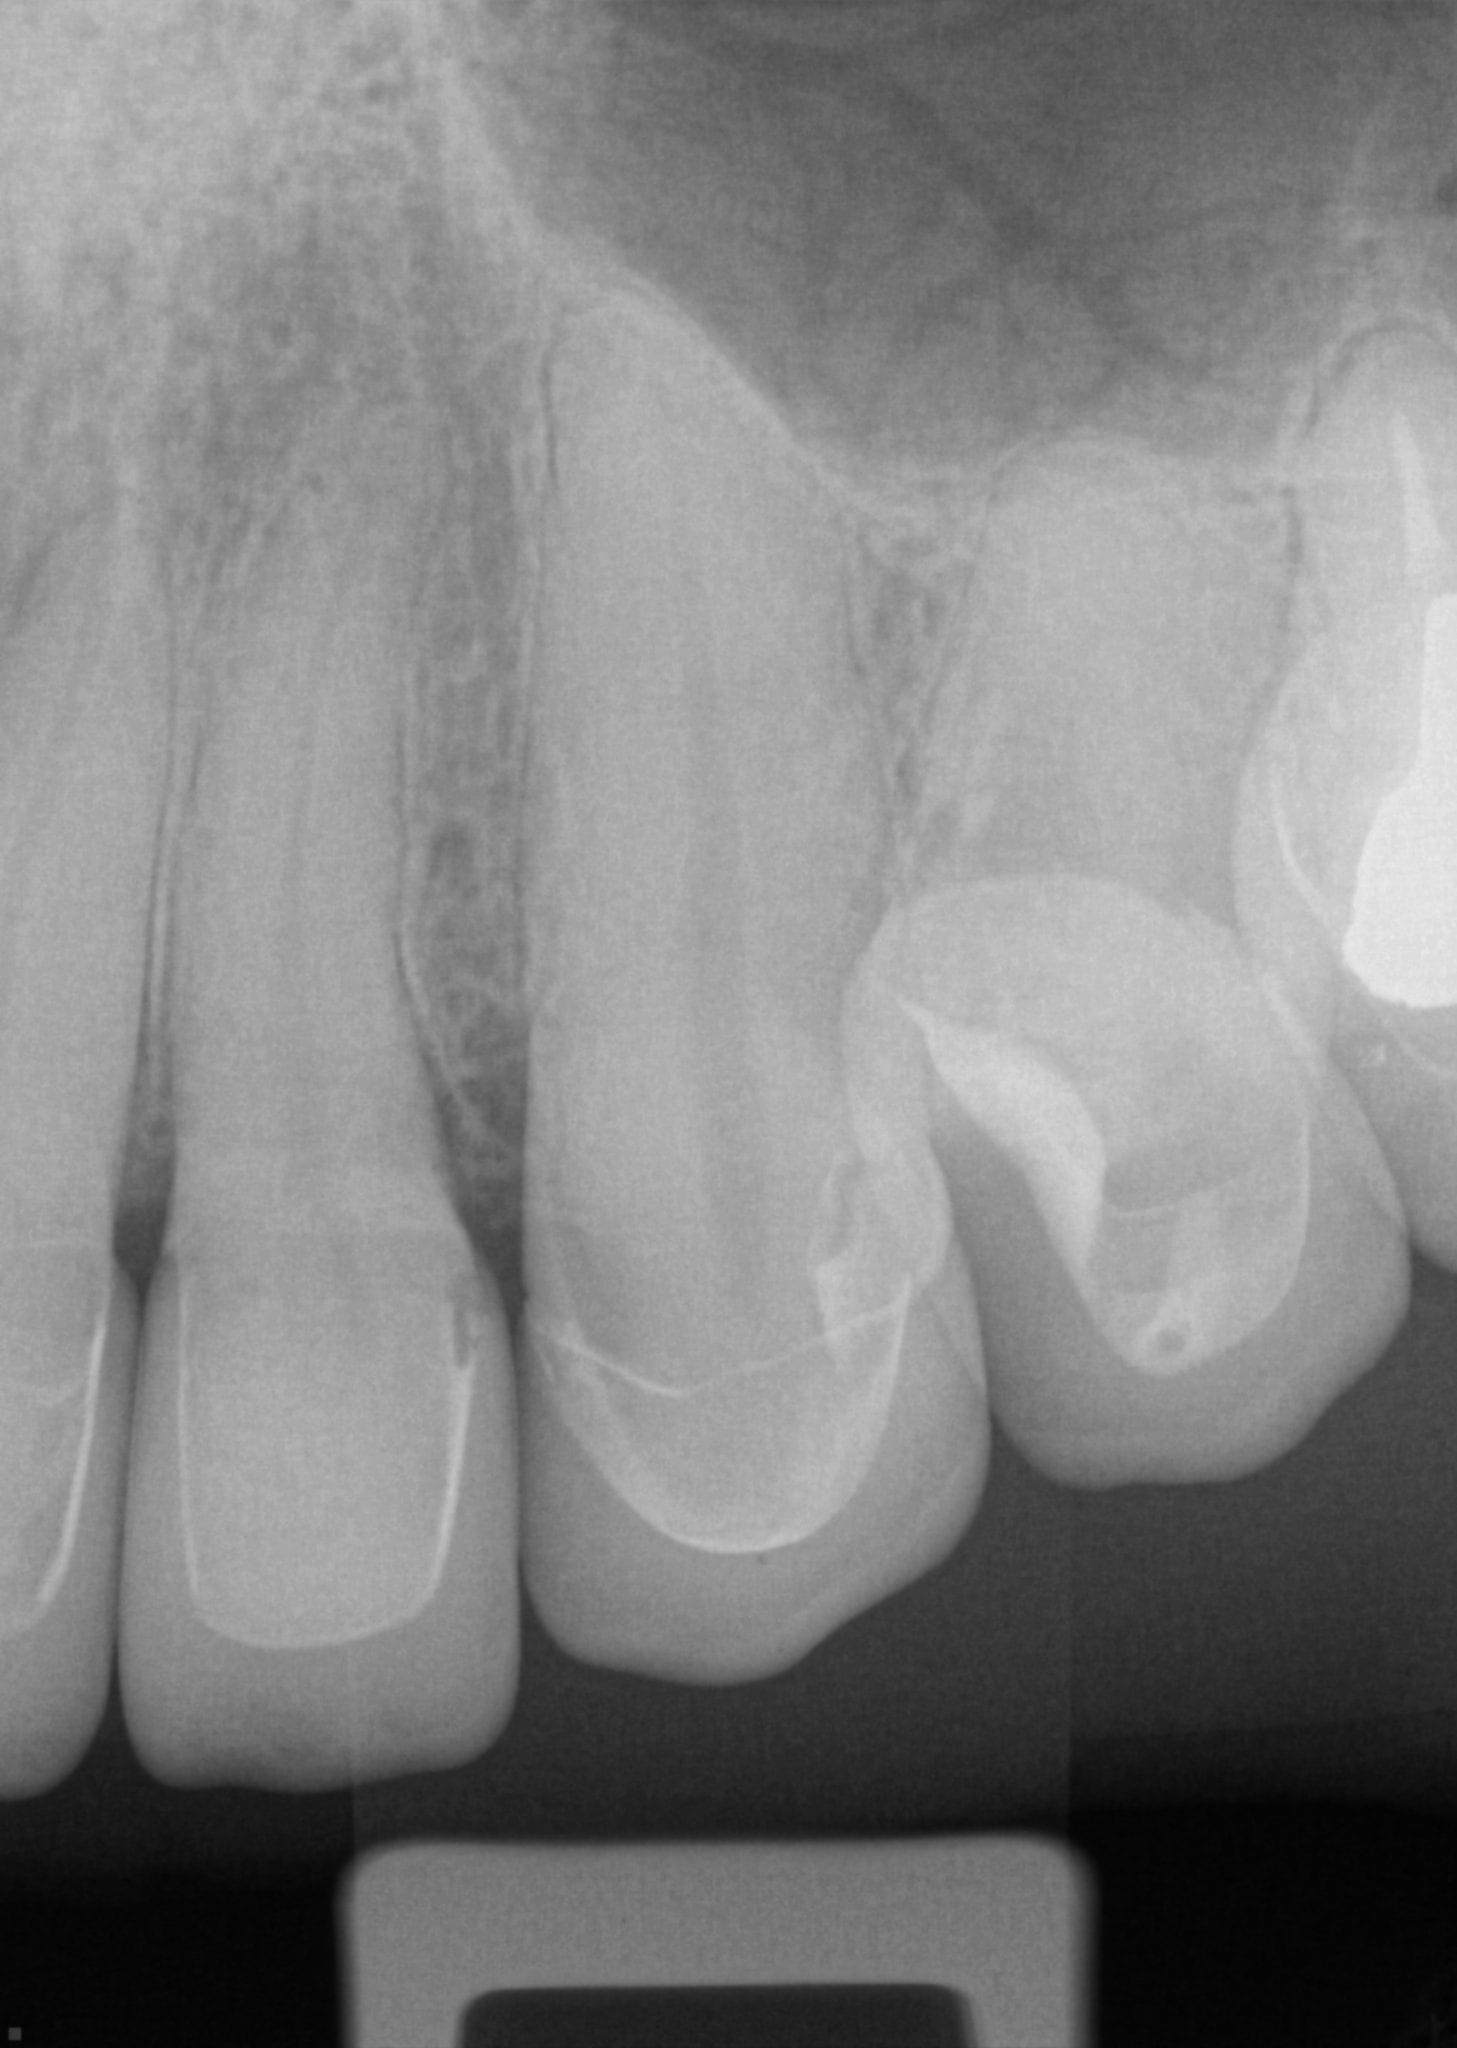

One Month Post Op with Radiographs